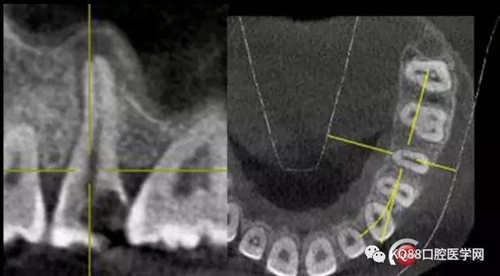

25遠(yuǎn)中鄰牙合面齲壞達(dá)髓腔,引起的牙髓炎,之后發(fā)展成為根尖炎的一個(gè)常見(jiàn)病例,上頜前磨牙,一看,心理都會(huì)覺(jué)得有啥啊,兩個(gè)根管,開(kāi)髓后,直接擴(kuò)了,不會(huì)有任何壓力,幸運(yùn)的是我們有CT,所以我就開(kāi)始都會(huì)定位下根管口,然后看到的事情告訴我其實(shí)上頜前磨牙不一定有我們想象的那么簡(jiǎn)單。

這兩張角度的截圖告訴我們這個(gè)牙齒一個(gè)典型的Y型根管,髓腔非常巨大,從根管口看,貌似一個(gè)根管口,但是根管銼下去以后,會(huì)兩個(gè)方向角度的分開(kāi)。因?yàn)槲覀儸F(xiàn)在都是常規(guī)的機(jī)擴(kuò)與熱牙膠充填,建立直線根管口的暴露就變得非常重要,必須直線視野下操作,機(jī)擴(kuò)才不會(huì)發(fā)生扭曲折斷。目前市面上的根管銼有很多,M3,S3等,而此次我使用的是歐羅德卡PLEX軟銼,因?yàn)槭强谇?8贈(zèng)送我的,所以我就先嘗試的使用了一下,我不會(huì)單方面的去評(píng)價(jià)比別的好,我覺(jué)得預(yù)備方法對(duì)了,都會(huì)很不錯(cuò),只能說(shuō)一句這個(gè)用起來(lái)軟銼對(duì)后牙的預(yù)備確實(shí)不錯(cuò)。根管預(yù)備,常規(guī)我都會(huì)先C銼疏通,如果直接15號(hào)很有可能會(huì)在根尖方形成臺(tái)階,以后就很難再下去了,當(dāng)C銼到達(dá)根尖孔后,予以初步測(cè)量長(zhǎng)度,在用疏通機(jī)擴(kuò)針通入,然后一步步規(guī)范化開(kāi)始,逐級(jí)預(yù)備,一個(gè)簡(jiǎn)單的經(jīng)驗(yàn),如果當(dāng)使用的銼不容易到達(dá)根尖時(shí),不要著急,用上一號(hào),繼續(xù),再回來(lái),就可以了,不然形成臺(tái)階,就很難操作了,常有人會(huì)覺(jué)得擴(kuò)根時(shí),突然發(fā)現(xiàn),下不去了,排除斷針的可能性的話,臺(tái)階是最重要的,擴(kuò)根時(shí),1%次氯酸鈉變沖洗,變預(yù)備,防止碎屑推出根尖孔,我沖洗常使用1%次氯酸鈉與蒸餾水,再充填前,會(huì)使用EDTA沖洗液去除根管壁油污。